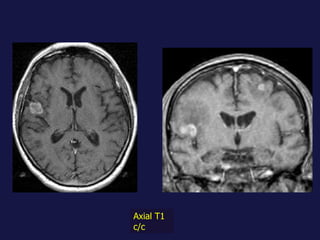

Metástasis. Cerebro. Hueso. Hígado. Suprarrenales.

Axial T1 c/c

Metástasis al pulmón. El pulmón y el hígado son los mas FREC. Pueden tener varios tamaños. Imágenes nodulares, únicas o múltiples. Pueden cavitarse y calcificación.

Metástasis. Cerebro. Hueso.Hígado. Suprarrenales.